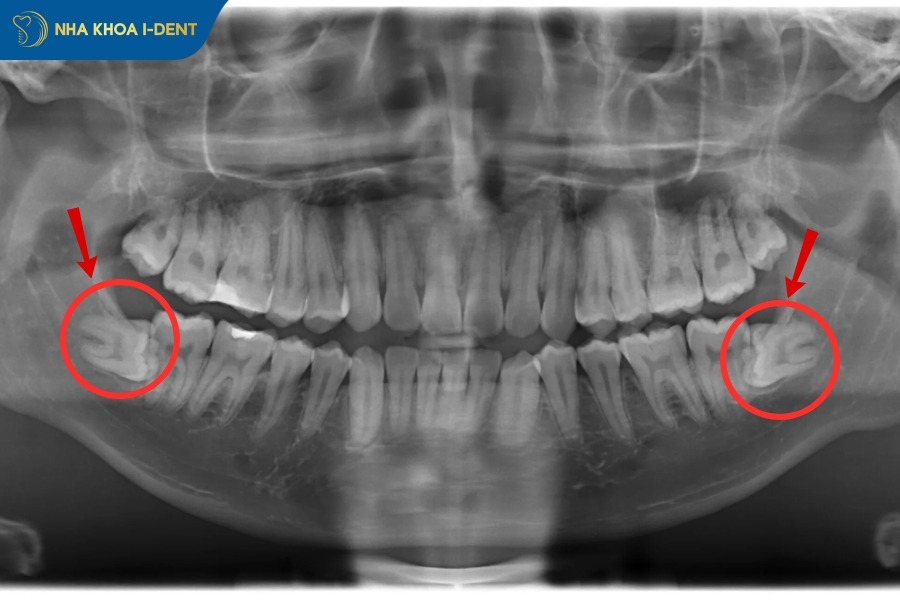

Trường hợp răng khôn mọc lệch, đâm thẳng vào má hay các răng kề cạnh, hoặc răng mọc nằm ngang một góc 90 độ bắt buộc phải nhổ răng khi niềng. Do răng khôn mọc lệch hoặc nằm ngang sẽ có xu hướng đâm trực tiếp vào răng số 7 và tạo áp lực liên tục lên các răng bên cạnh, gây đau nhức, viêm nướu, sâu răng số 7 cho nên cần nhổ răng số 8 để bảo vệ răng số 7.

Đặc biệt nếu răng mọc ngang 90 độ nằm hoàn toàn trong cung hàm sẽ tác động đến lực kéo của mắc cài và dây cung niềng răng, làm giảm quá hiệu quả điều trị và kéo dài thời gian niềng.